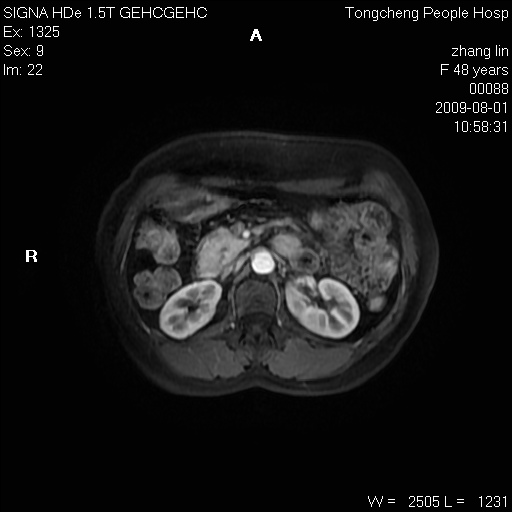

女,48岁。健康体检,彩超发现右肾占位性病变。平素健康。

临床诊断:右肾占位性病变,性质待定(囊肿?肿瘤?)。

上中腹部mr平扫+增强扫描,图像如下:

右肾上极见一类圆形病灶,t1wi呈等信号t2wi呈等高混杂信号,三期增强无强化,边界清---考虑囊肿出血。

同反相位均表现为等信号,病变无强化,考虑含蛋白的囊肿可能,弥散加权相或许有些帮助,